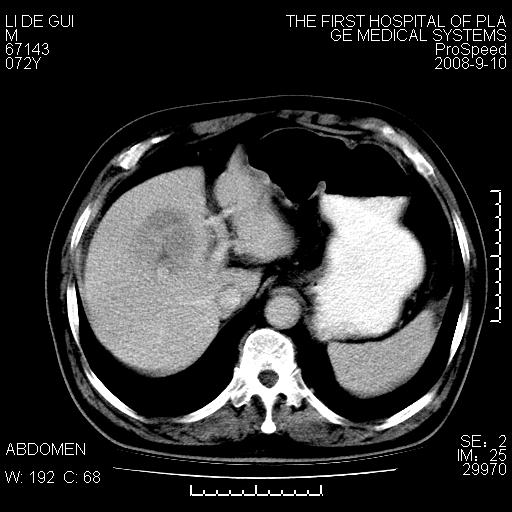

标题: CT17988:腹部肿块两年,肿块大小无变化,患者无不适,自我 [打印本页]

标题: CT17988:腹部肿块两年,肿块大小无变化,患者无不适,自我

胆囊占位性病变(黄色肉芽肿性胆囊炎?)。

考虑-----胆囊血肿机化或胆囊癌或腺肌增生症------增强

不好说,期待增强图像。

胆囊占位性病变,增强。